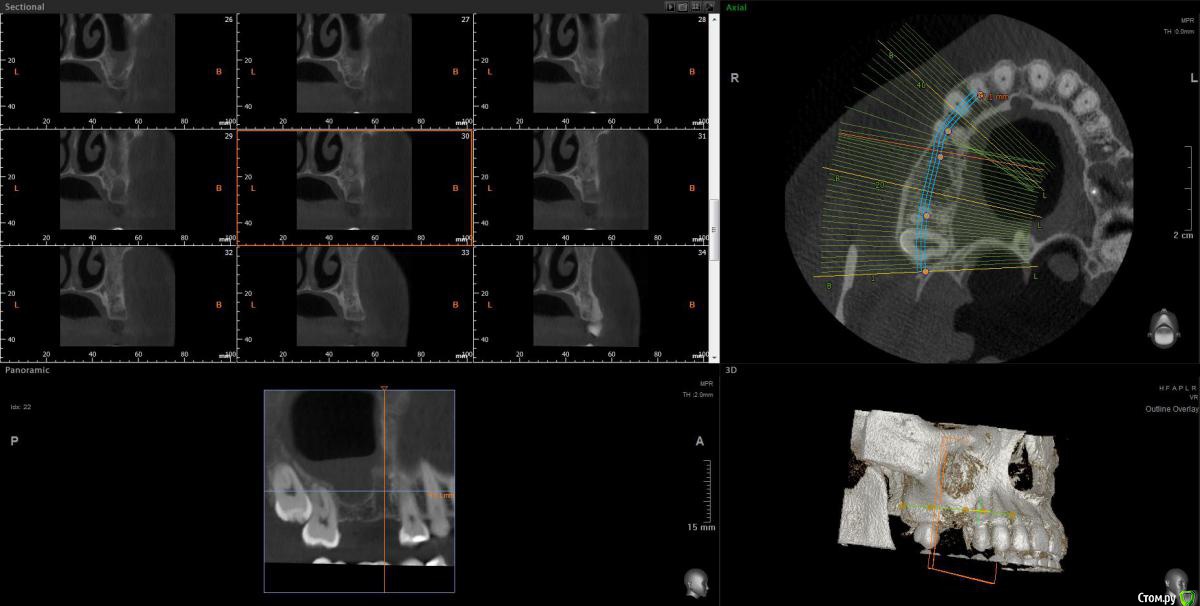

wladdX Опубликовано 30 июня, 2020 Поделиться Опубликовано 30 июня, 2020 Несколько скриншотов из КЛКТ 2 Ссылка на комментарий

колесников Опубликовано 30 июня, 2020 Поделиться Опубликовано 30 июня, 2020 Есть жидкость в пазухе на момент снимка. Можно только предполагать что является причиной воспаления,полной картины нет. Возможно это рельеф дна пазухи. В области 6ки углубление,где как в колодце застаивается слизь и прочее что попадает в полость и естественного дренажа не происходит. Я бы рекомендовал поставить 2 импланта 5,6. В области 6го провести закрытый синуслифтинг. Рельеф дна пазухи выровняется и вероятно обострений больше не будет. По крайней мере процессы происходящие в пазухе никак не повлияют на имплантацию,тогда как имплантация может купировать процессы в пазухе. Ссылка на комментарий

Оvzaika Опубликовано 1 июля, 2020 Автор Поделиться Опубликовано 1 июля, 2020 Несколько скриншотов из КЛКТ 25_1.jpg25_2.jpg26_1.jpg26_2.jpgH_M.jpgСпасибо! Ссылка на комментарий

Оvzaika Опубликовано 1 июля, 2020 Автор Поделиться Опубликовано 1 июля, 2020 Есть жидкость в пазухе на момент снимка. Можно только предполагать что является причиной воспаления,полной картины нет. Возможно это рельеф дна пазухи. В области 6ки углубление,где как в колодце застаивается слизь и прочее что попадает в полость и естественного дренажа не происходит. Я бы рекомендовал поставить 2 импланта 5,6. В области 6го провести закрытый синуслифтинг. Рельеф дна пазухи выровняется и вероятно обострений больше не будет. По крайней мере процессы происходящие в пазухе никак не повлияют на имплантацию,тогда как имплантация может купировать процессы в пазухе.добрый день! пока есть воспаление за имплантацию 6-ки никто не берется, вчера один врач предложил сделать синусотомию под местным наркозом убрать все что будет в пазухе подождать месяц заживления и потом делать синус-лифтинг. Ссылка на комментарий

колесников Опубликовано 1 июля, 2020 Поделиться Опубликовано 1 июля, 2020 добрый день! пока есть воспаление за имплантацию 6-ки никто не берется, вчера один врач предложил сделать синусотомию под местным наркозом убрать все что будет в пазухе подождать месяц заживления и потом делать синус-лифтинг. как ни абсурдно звучит,я бы предложил вначале провести имплантацию с синуслифтингом,а после понаблюдать и возможно санировать пазуху. Если сделать как Вам предлагали,есть вероятность что пауза будет не месяц а больше,а за это время в эту ямку снова соберётся жидкость с последующим инфицированием. Нет ямки-нет условий для застоя жидкости. Ссылка на комментарий